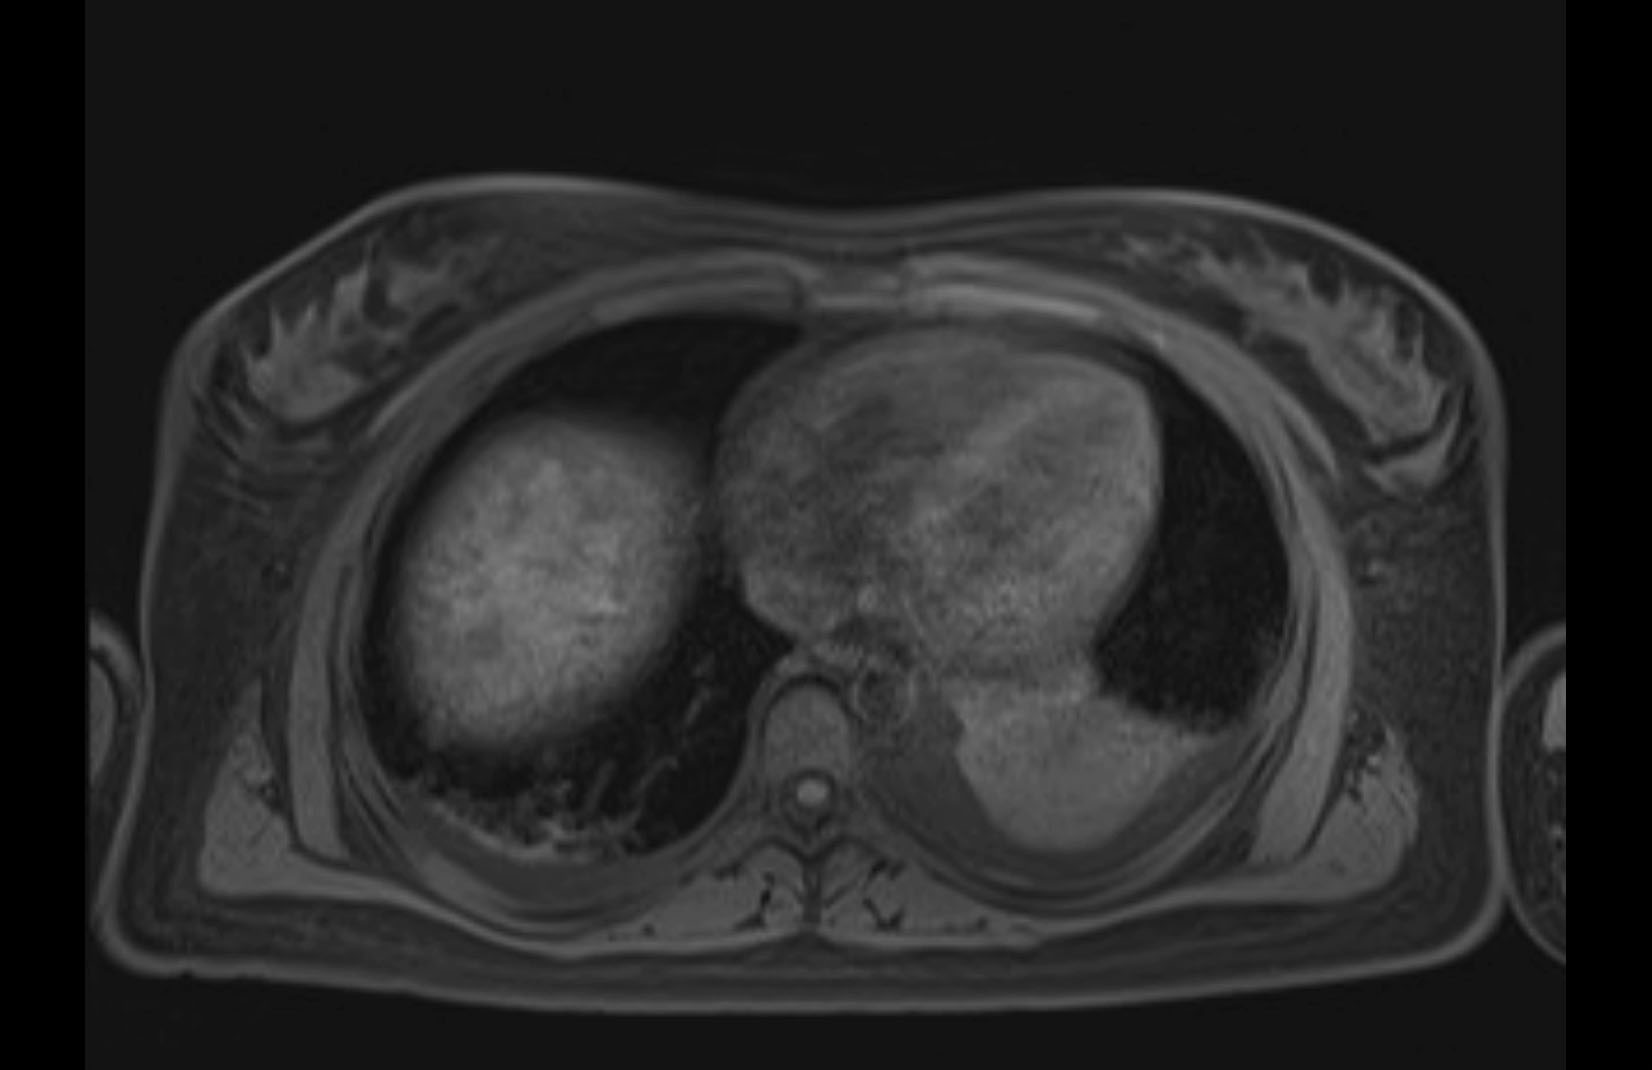

MRI T1

MRI T2